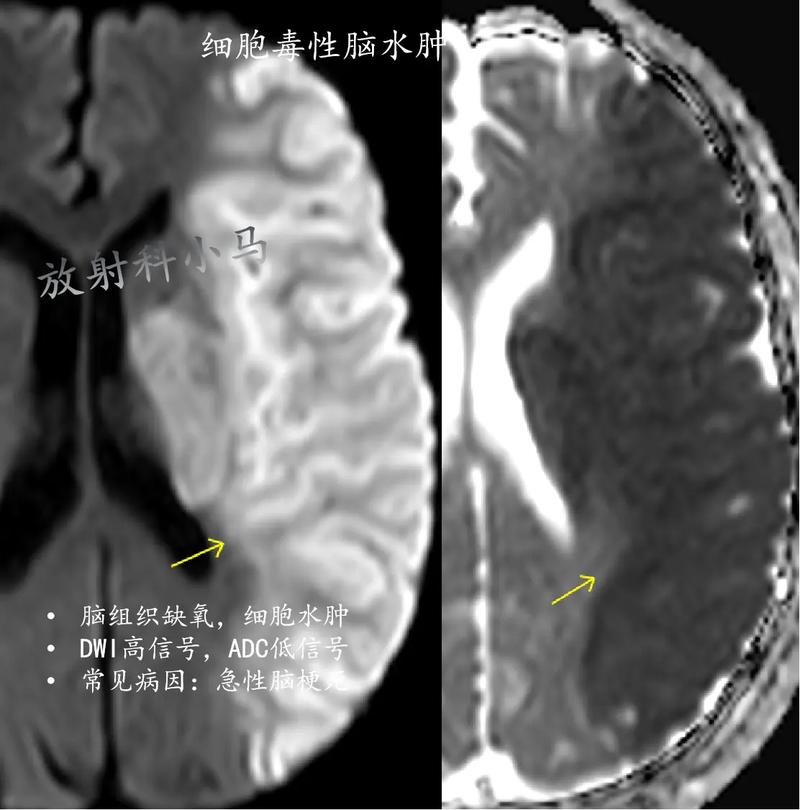

第一阶段:细胞毒性水肿 (Cytotoxic Edema) - 发生在早期(数小时内)

- 原因: 脑梗后,局部血管堵塞,脑细胞(神经元、胶质细胞)因缺血缺氧,能量(ATP)耗尽。

- 过程: 细胞膜上的“钠钾泵”(Na+/K+-ATPase)失效,这个泵的正常工作是把细胞内的钠离子泵出去,把细胞外的钾离子泵进来,以维持细胞内外的离子平衡,泵失效后,钠离子大量涌进细胞内,为了平衡渗透压,水分也随之进入细胞内,导致细胞像气球一样肿胀。

- 特点: 这个阶段主要是细胞本身“喝水”肿胀,细胞间隙是正常的,这是最早期的水肿形式。